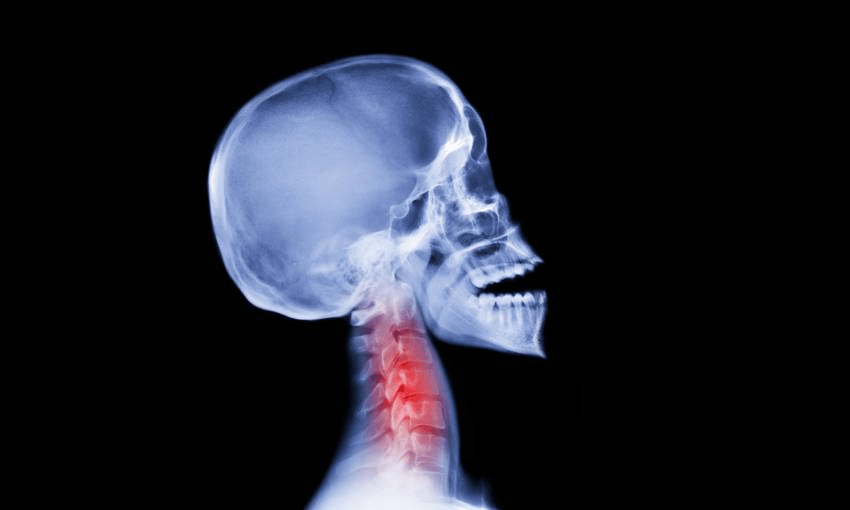

After a series of tests in hospital I was diagnosed with three fractured ribs, concussion and whiplash.

My head, inside my helmet, had conducted its own short arc at speed as my chest hit the ground first, followed by my head whipping around behind it to bounce once… twice… onto the tarmac at high speed while managing to stay connected to my body via my neck.

Vertebrae are not designed for this. Fortunately, crash helmets and heads are, but they mitigate, rather than prevent, damage.

Assorted scans and X-rays showed there were no brain bleeds and apart from a massive headache, the odd bout of losing consciousness and puking, an extremely sore neck and an inability to cough, sneeze, laugh or generally move without the feeling of a knife being driven into my side, I was OK, I thought.